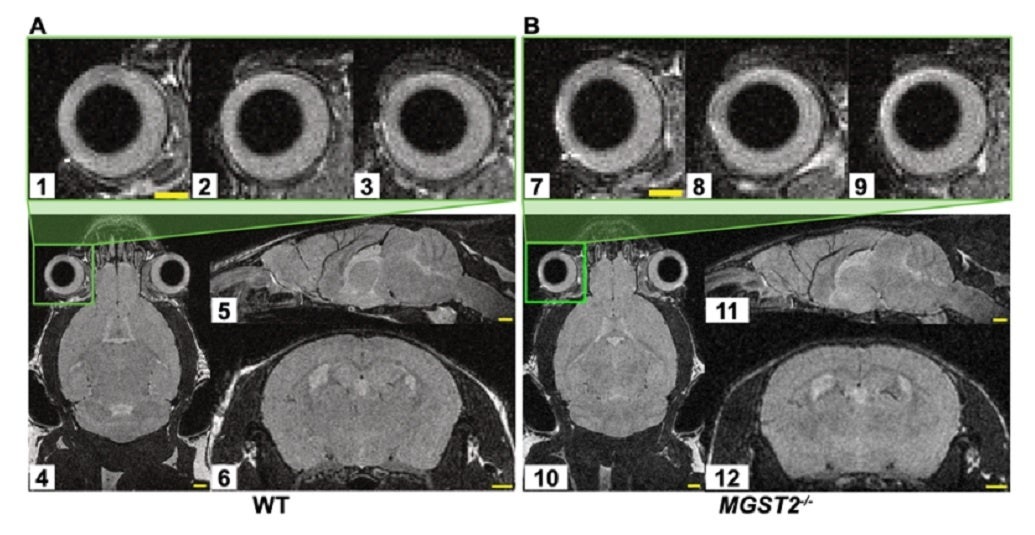

斜視の原因を明らかにするため、この候補遺伝子MGST2を働かなくさせたマウスを作成し、そのマウスの脳や眼球の形状を小動物用MRIで撮影して画像計測しました。

その結果、MGST2が機能していないマウスでは、眼球が上下左右にわずかながら拡大して眼球容積が有意に大きくなっていて、斜視の原因を考える手がかりが得られました。

野生型マウス(A)とMGST2欠損ホモ接合体マウス(B)の眼球(上段図)と脳全体(下段図)のMRI画像。岡山大学薬学部に設置されている小動物用MRI装置で撮影